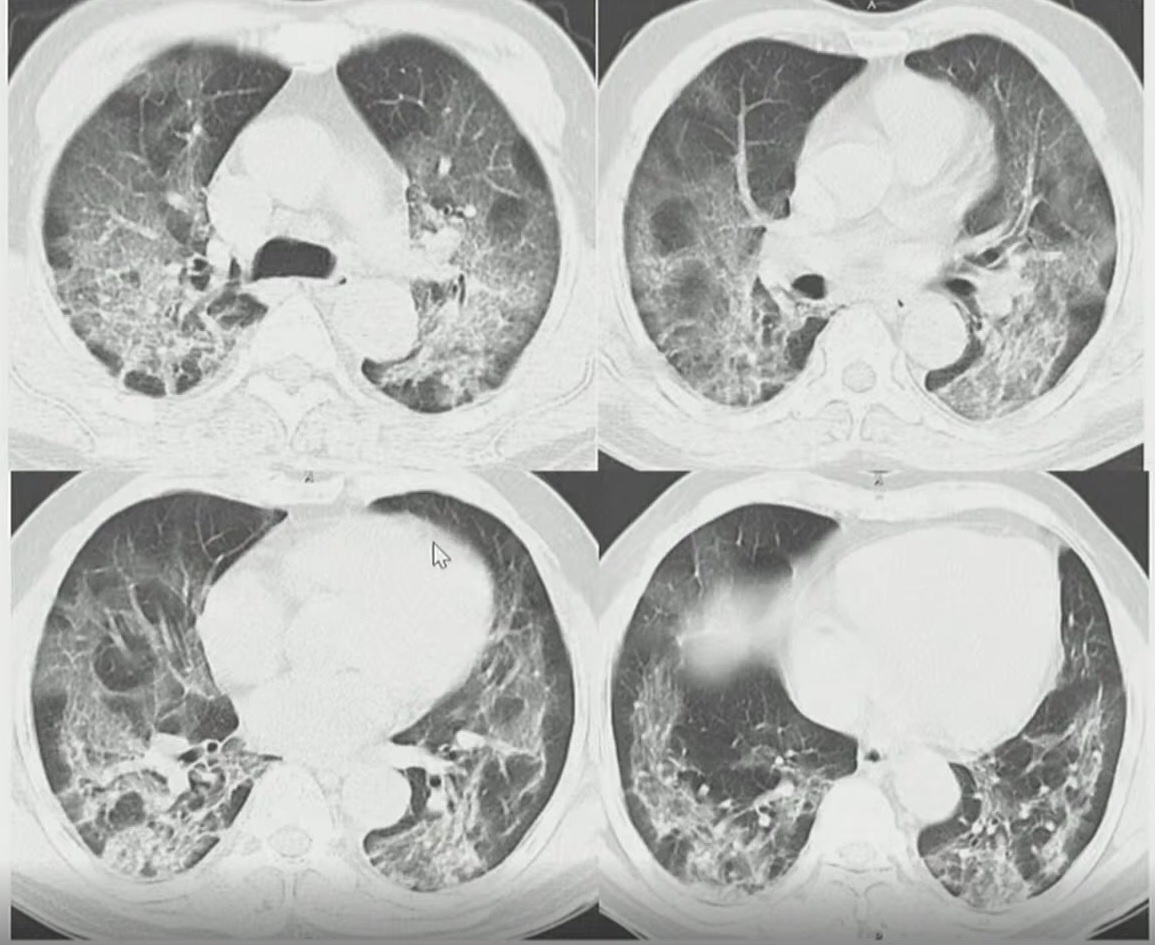

TS Lưu cung cấp hình ảnh X-quang phổi của BN867 được chụp hôm 9/8 - 9 ngày sau khi có biểu hiện bệnh. Hình ảnh cho thấy tổn thương phổi lan tỏa hai bên, chứng tỏ bệnh nhân bước vào giai đoạn đỉnh bệnh. Ngoài tình trạng kính mờ, phổi bị ảnh hưởng tạo hình tổ chức kẽ, lưới rõ rệt.

Hình ảnh X-quang và cắt lớp vi tính phổi của bệnh nhân 867. Ảnh: Bệnh viện Đại học Y Hà Nội. |

Phân tích hình ảnh cắt lớp vi tính, TS Lưu cho hay chúng rất điển hình ở bệnh nhân Covid-19 với kính mờ, phổi đông đặc, nằm ở các dải dưới màng phổi. Tổn thương phổi rất nặng, chiếm hơn 75% nhu mô.

“Nếu có bệnh nền đi kèm, người này có tiên lượng rất nặng”, TS Lưu nhận định đồng thời nhấn mạnh những người có tổn thương nhu mô phổi chiếm hơn 50% được xếp vào nhóm nguy cơ nặng về hô hấp.

Xem xét X-quang phổi của BN867, TS Lưu cho biết người này xét nghiệm rRT-PCR lần một âm tính nhưng với tổn thương phổi điển hình có thể khẳng định nguy cơ mắc Covid-19 rất cao. Các bác sĩ cần chú ý để phát hiện người mắc Covid-19, kể cả khi họ âm tính với SARS-CoV-2.